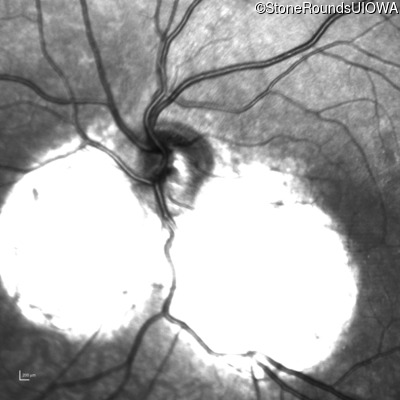

Infrared Fundus Photograph - Right - 20/40 +2

Exemplar